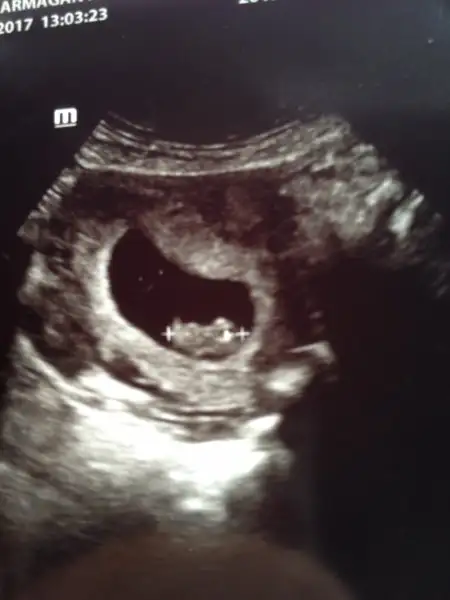

Canım mantıklı benim kesem sağda birde dakikada kalp atış hızına göre tahmin edilebiliyor kadınların kalp atışı erkeklere göre daha yüksek olduğun yüksekse kız aşşağılarda genelde erkek oluyormuş benimki 6+4 7mm dakikada 143 atış hızı kız çıktı tahminlerim birde sağda dedin haa tamam eminim şuan kızArkadaslar 7+1 de kalp atislarini duyduk sukur.0.95mm imis.her sey yolunda dedi.1 ay sonra 2 li tarama icin cagirdi. 3 aydan sonra kina da sac boyasi da serbestmis.gobegim cok sisiyordu.ama kilo almamisim hatta 700 gr vermisim.ustelik hic kusmadim sayilir.ilk basta adet olamamanin verdigi bi su tutulmasi mi vardi bilmiyorum.yada ictigim su miktari artti ara ogun yaptim.o yuzden belki vermisim gibi oldu.bilmiyorum.bu gece midem cok kotu.sanki dr.gitmeyi bekliyormus. Bu arada kesenin icindeki sag yada solda durmasina gore cinsiyet tahminleri var nette.iki cocuklu olanlarin ilk cocuklarinda tutuyormu? elinize alinca fotosunu kesenin sagindaysa kizmis hesapta.benim solda gozukuyor.sacmalik da olabilir.

Ay ona bakmadımHayirli olsun canim.kesenin nerede oldugu degil bebegin kesenin icinde sagdami soldami oldugu onemliymis.bebegin kesenin icinde sagda mi? Benim dr kalp atis hizini soylemedi.

Ama canım doktorun baktığı ekranda solda duruyormuş benim baktığımda yönü değişik oluyor ya sağda gözüküyordu şimdi oturdu sen kendininkini doktorun ekranından mı kendi ekranındanmı gördün acaba şimdide erkek heycanı sardı en iyisi ikiz olsada ikiside olsaHayirli olsun canim.kesenin nerede oldugu degil bebegin kesenin icinde sagdami soldami oldugu onemliymis.bebegin kesenin icinde sagda mi? Benim dr kalp atis hizini soylemedi.

Valla benim yeğenim ultrason kağıdının solunda yatıyordu erkekti şimdi benimde solda yatıyor acaba diyorumAma canım doktorun baktığı ekranda solda duruyormuş benim baktığımda yönü değişik oluyor ya sağda gözüküyordu şimdi oturdu sen kendininkini doktorun ekranından mı kendi ekranındanmı gördün acaba şimdide erkek heycanı sardı en iyisi ikiz olsada ikiside olsa

Acaba ihtimali yüksek erkek olabilir olasılıkda olsa yüksekValla benim yeğenim ultrason kağıdının solunda yatıyordu erkekti şimdi benimde solda yatıyor acaba diyorum

Ekrani degil.fotografina bakinca fotografta kesenin sagindaysa kiz solundaysa erkek diyor.fotograf elinde duracak.kendi yonune cevirme karninin ustune koyup.fotografa gore sag sol yani.Ama canım doktorun baktığı ekranda solda duruyormuş benim baktığımda yönü değişik oluyor ya sağda gözüküyordu şimdi oturdu sen kendininkini doktorun ekranından mı kendi ekranındanmı gördün acaba şimdide erkek heycanı sardı en iyisi ikiz olsada ikiside olsa